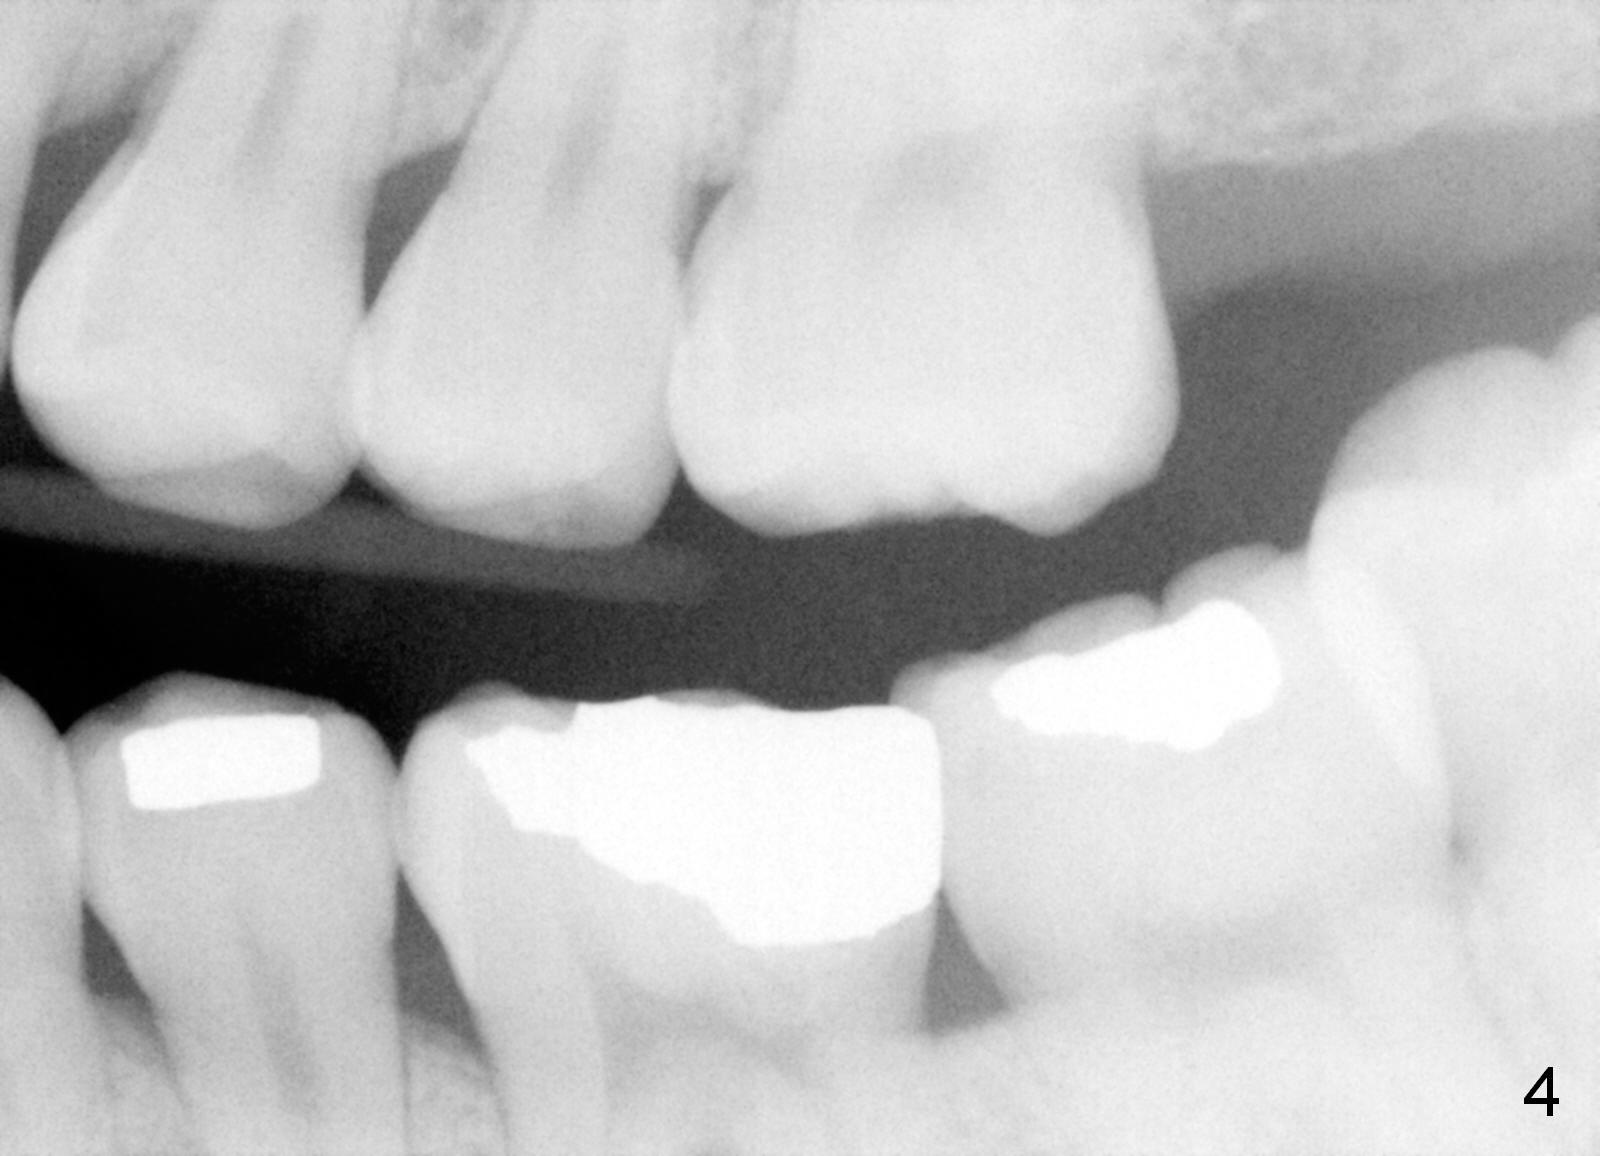

The panoramic X-ray (Fig.1) was taken on 12/12/2011 when the teeth #15 and 16 were extracted. The teeth #1 and 2 were removed half a year later. Bitewings (Fig.2-5), PAs (Fig.6,7) and upper occlusal mirror photo were taken on 02/11/2015. Pay attention to Fig.2.